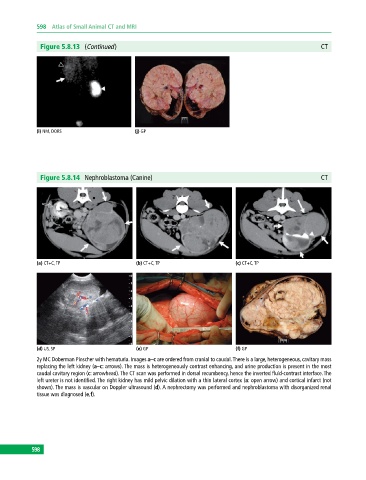

Figure 5.8.14 Nephroblastoma (Canine) CT

(a) CT+C, TP (b) CT+C, TP (c) CT+C, TP

(d) US, SP (e) GP (f) GP

2y MC Doberman Pinscher with hematuria. Images a–c are ordered from cranial to caudal. There is a large, heterogeneous, cavitary mass

replacing the left kidney (a–c: arrows). The mass is heterogeneously contrast enhancing, and urine production is present in the most

caudal cavitary region (c: arrowhead). The CT scan was performed in dorsal recumbency, hence the inverted fluid‐contrast interface. The

left ureter is not identified. The right kidney has mild pelvic dilation with a thin lateral cortex (a: open arrow) and cortical infarct (not

shown). The mass is vascular on Doppler ultrasound (d). A nephrectomy was performed and nephroblastoma with disorganized renal

tissue was diagnosed (e,f).